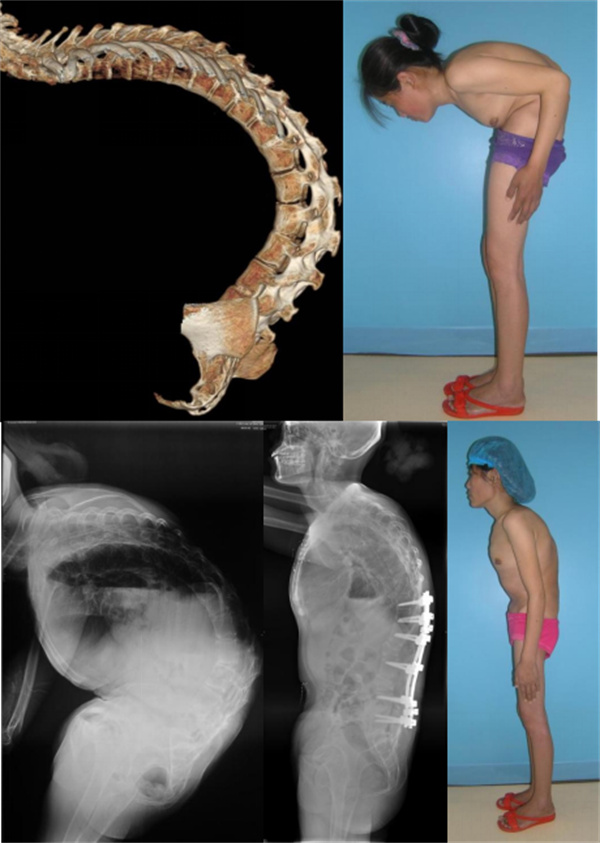

严重强直性脊柱炎后凸

该患者存在严重的脊柱后凸,且颈椎自发融合,无活动度,困难气道,插管难度大。术前体位摆放困难,颈椎、肩关节、髋关节损伤风险较大。术中高级别截骨,脊髓损伤风险较大。手术时间长,出血多,术中需随时调整体位,颈椎损伤风险较大。强制性脊柱炎患者自身免疫力低,椎体骨质疏松,术后感染、螺钉拔出等风险较大。